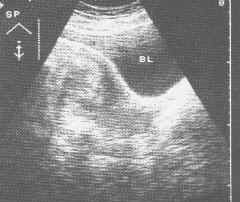

(1)B超檢查:B超檢查可以了解子宮大小、子宮內膜厚度、有無回聲不均或宮腔內贅生物,有無肌層浸潤及其程度等,其診斷符合率達80%以上。由於子宮內膜癌患者肥胖者甚多,因此經陰道超聲比經腹部超聲更具優勢。由於B超檢查方便及無創,因此成為診斷子宮內膜癌最常規的檢查,也是初步篩查的方法。

子宮內膜癌(B超)在歐洲子宮內膜癌占子宮癌腫的10~25%,美洲為20~25%,日本為3~8%,中國為0.99~9.9%。據世界23個國家和地區的調查,美國、西德發病率為3.38~45.8/10萬,而印度、日本則為1.7~1.8/10萬;上海某居民區普查,宮頸癌發病率為11.3/10萬,子宮內膜癌為0.85/10萬,二者之比為13.3∶1.Parson報告子宮內膜癌的發生率在40歲的婦女為10/10萬,50歲者為40/10萬,60歲者為85/10萬。